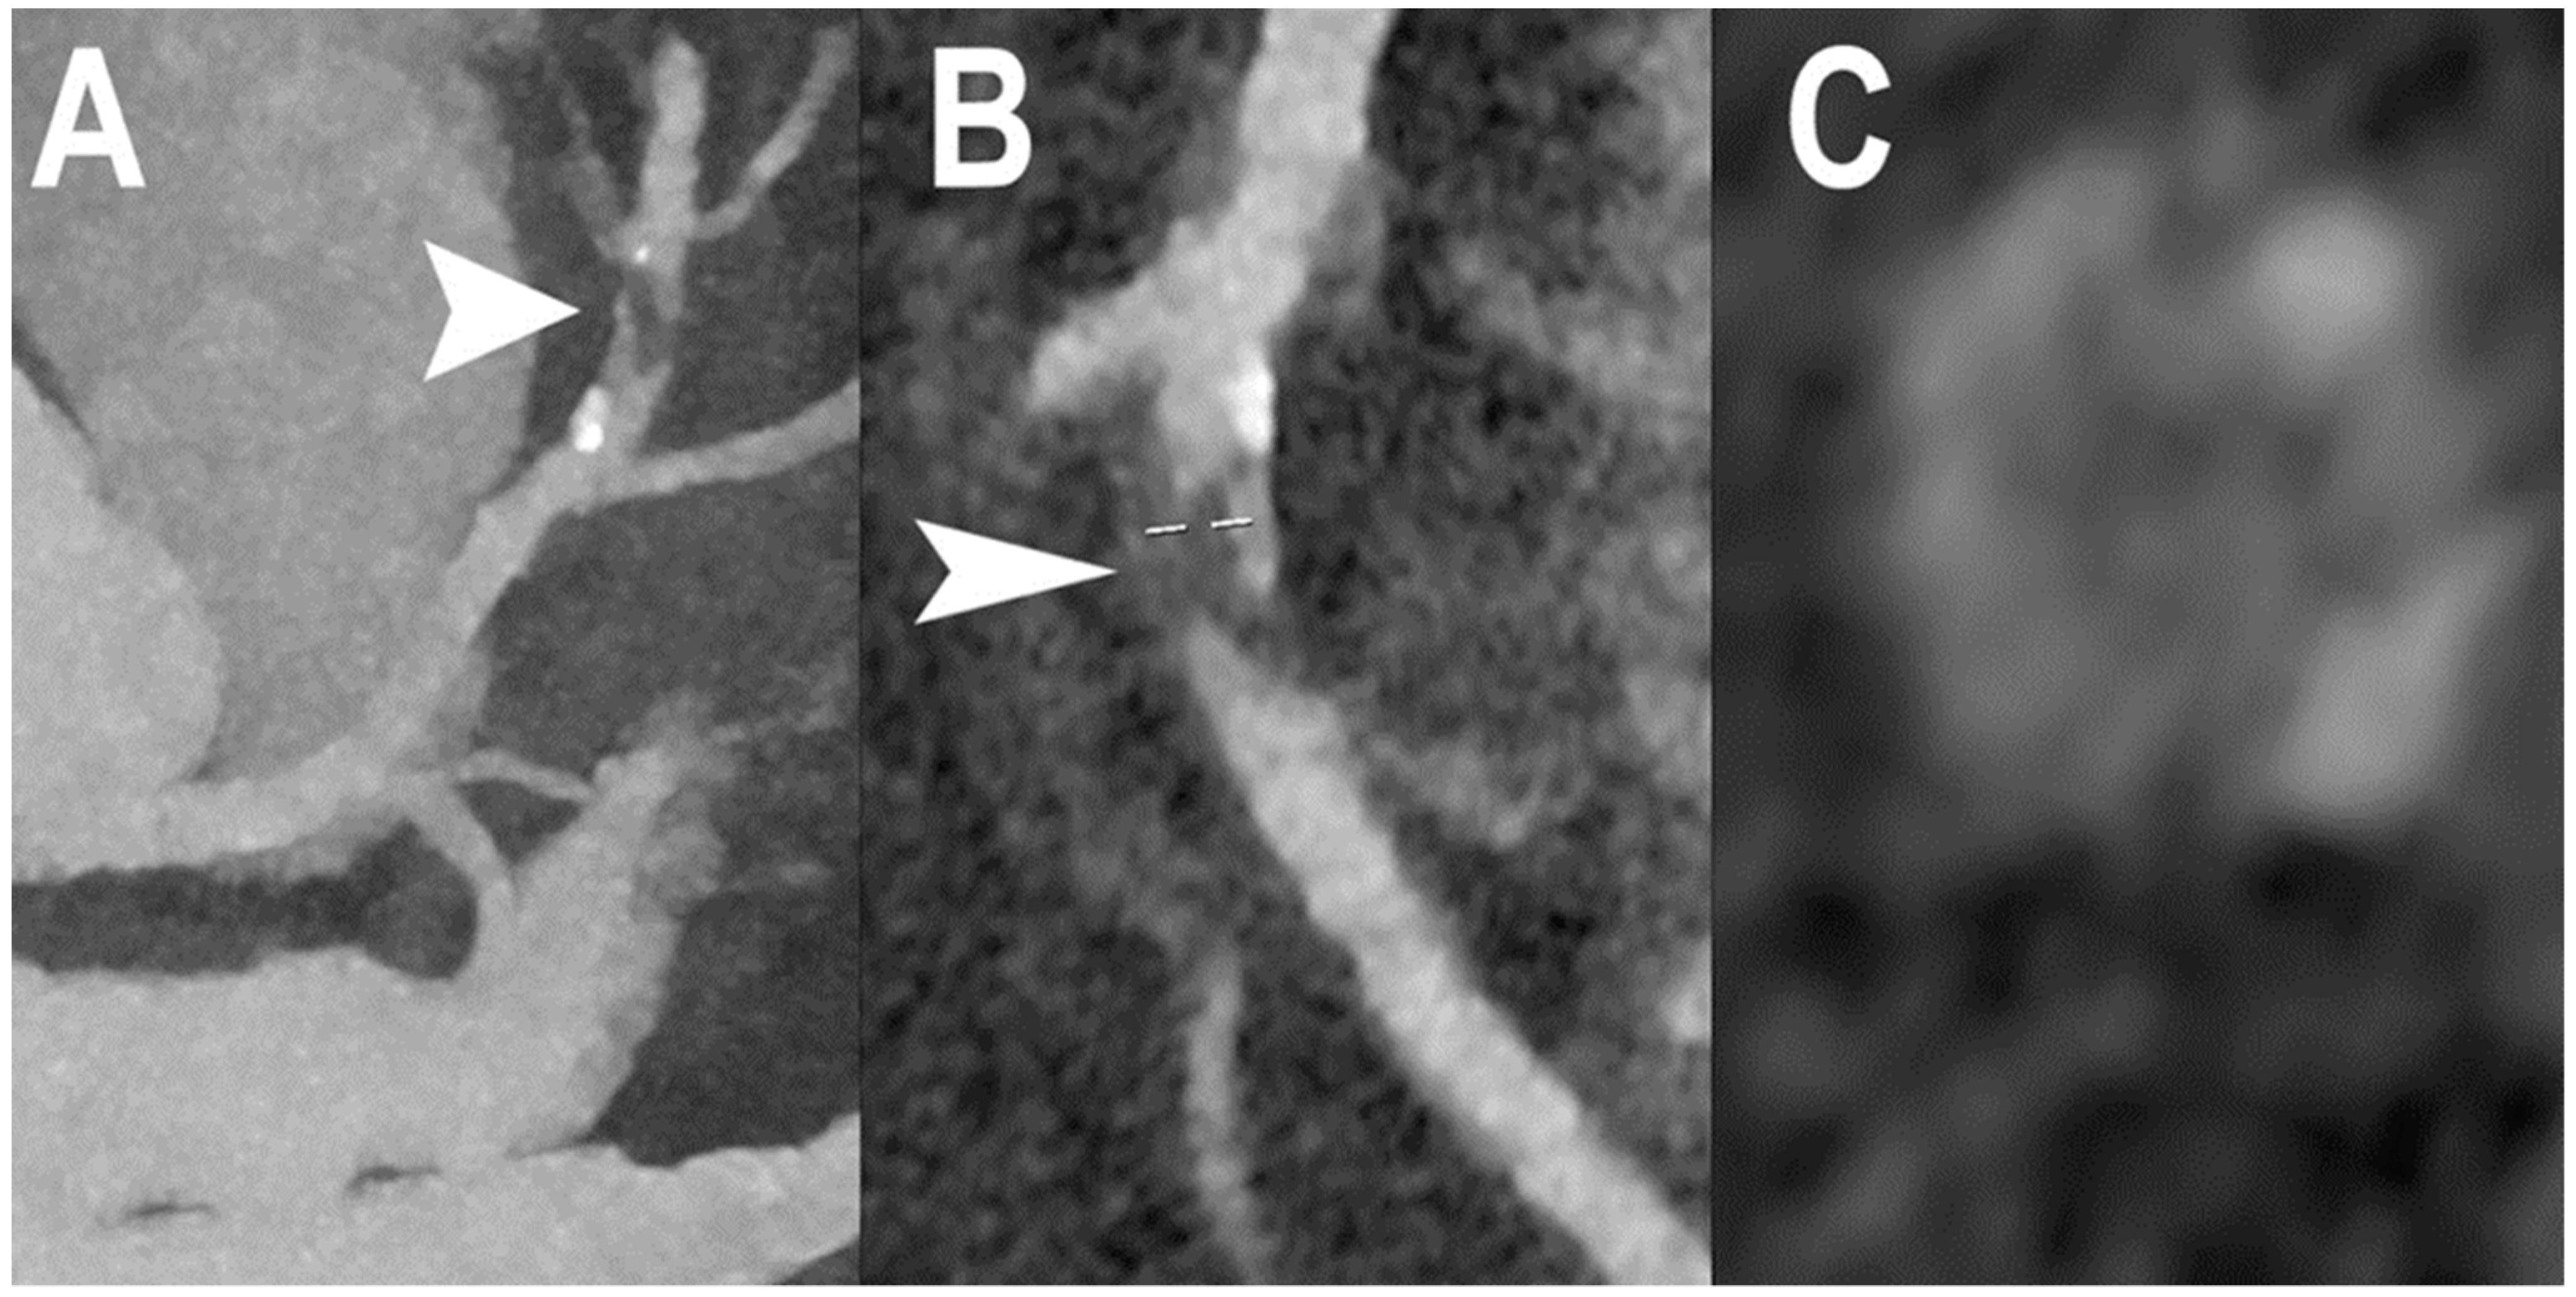

| Boccalini et al. [33] | 2022 | In vivo (human) | 8 | Coronary stent Dose reduction | Superior stent and lumen visibility with fewer blooming artifacts and lower dose radiation for PCCT versus conventional CT. |

| Mannil et al. [23] | 2018 | In vitro | Coronary stent | In comparison with EID-CT, PCCT offered superior in stent visibility, fewer blooming and partial volume artifacts, with a lower increase in the attenuation of the lumen inside the stent. | |

| Symons et al. [34] | 2018 | In vitro | Coronary stent | Better luminal depiction with lower image noise in PCCT compared to EID-CT. | |